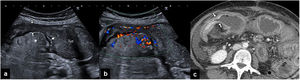

Cuando la pared intestinal es patológica pierde elasticidad, y eso se manifiesta como una rigidez o dificultad en la compresión. Este es uno de los hallazgos más útiles en ecografía para reconocer la inflamación, como en el caso de la apendicitis. Por otra parte, cuando la pared está engrosada y rígida, puede provocar estenosis de la luz, como ocurre en la enfermedad de Crohn o en los tumores intestinales (fig. 7).

a) Ecografía del vacío derecho en un paciente con enfermedad de Crohn, que muestra un asa de intestino delgado dilatada y con contenido intestinal en la luz. Distalmente, se aprecia un engrosamiento homogéneo de la pared (flecha fina), que condiciona una estenosis (flechas gruesas), provoca obstrucción y asocia inflamación de la grasa que rodea la porción mesentérica del asa (asterisco). b) La ecografía Doppler color del mismo segmento demuestra una marcada hiperemia de la pared del asa estenótica y de los vasos mesentéricos. c) Tomografía computarizada abdominal con contraste intravenoso, que muestra la dilatación de las asas (a) y un realce estratificado de la pared de la estenosis inflamatoria (flechas).